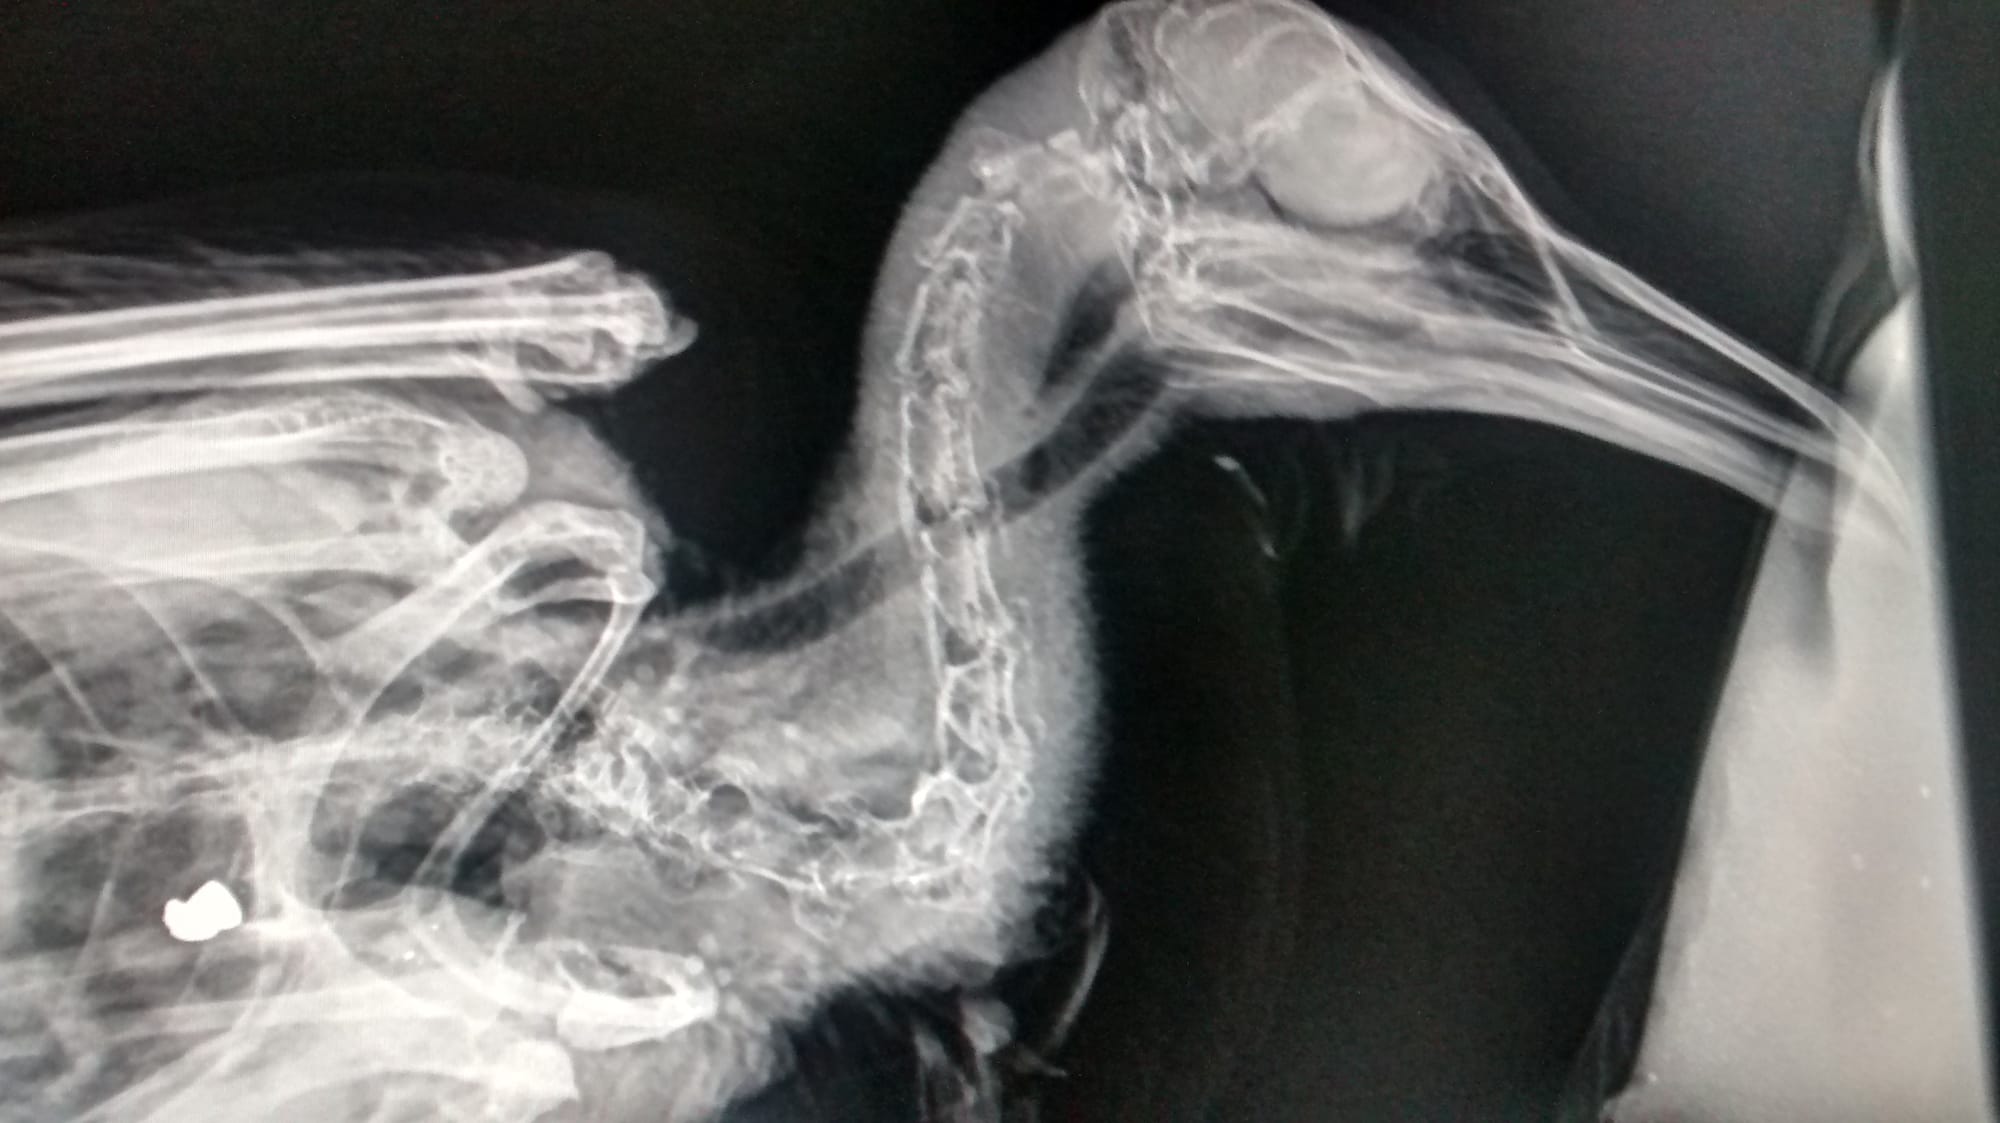

The Herring Gull was found with a gun pellet lodged in its chest in Paton Close, just off Saughall Massie Road, on Saturday.